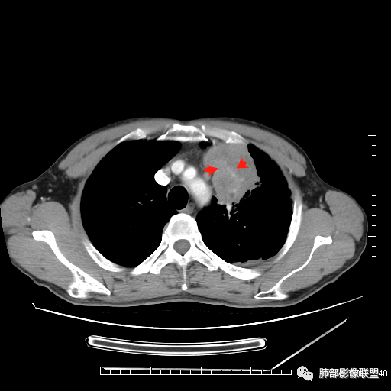

1.左肺上叶尖后段体积变化不大,病灶长轴沿支气管血管束向肺门侧生长,

2.病灶外围大,内带小,外朝内蔓延

3.病灶边缘以收缩为主,局部稍膨隆,

4.病灶整体轻中度强化,强化较均匀,局部见多个管状低密度影,边界清,考虑支气管粘液栓;病灶局部可小灶样的低密度区,未见强化,考虑坏死灶,坏死灶周围见明显强化的壁,壁清楚、光整,未见中断,倾向炎性肉芽肿的坏死;

5.病灶内血管部分走形自然,部分走形僵直、粗细不均,提示病灶有部分破坏力,但是不强;

6.病灶与纵隔胸膜呈“糊墙”样改变,倾向炎性病灶;

6.纵隔淋巴结肿大,密度均匀,强化均匀;